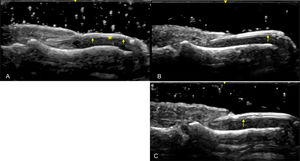

Ultrasound is especially useful for detecting early psoriatic nail changes, such as minimal thickening of the nail bed or slight loosening of the ventral plate (Fig. 6). As the disease progresses, more pronounced alterations occur, including thickening of both the ventral and dorsal nail plates. In these advanced stages, the trilaminar structure of the nail plate, characteristic of healthy nails, is completely lost. The nail plate becomes thickened, wavy, and hyperechoic, with an inhomogeneous appearance [133,137] (Fig. 7). Power Doppler (PD) is particularly valuable for assessing inflammation in the nail matrix and bed, grading vascularization on a scale from 0 to 3, where higher values indicate greater inflammation [20].

Fig. 7.(A–D) Late Psoriatic Nail Changes (Longitudinal view). Sonographic image obtained using Logiq e US system with an 8–18i MHz linear transducer. Grayscale ultrasound reveals pronounced thickening of both the ventral and dorsal nail plates, resulting in the complete loss of the normal trilaminar structure characteristic of healthy nails. The nail plate appears as a single hyperechoic layer with inhomogeneous thickness (arrow), while the nail bed is significantly thickened (asterisk). In these advanced stages, the nail plate becomes thickened, wavy, and hyperechoic, exhibiting an overall inhomogeneous appearance.